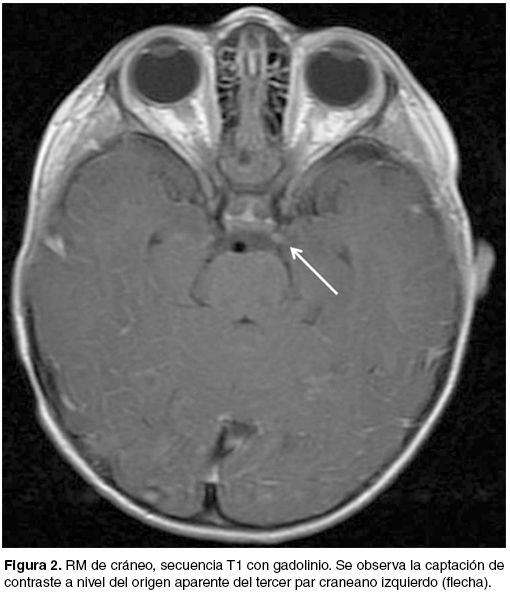

La RM con gadolinio muestra engrosamiento del tercer par craneano izquierdo con captación de contraste (Figura 2). Con planteo de neuropatía oftalmopléjica dolorosa recurrente, se inicia tratamiento con prednisolona a 2 mg/kg/día durante 5 días. Al término del tratamiento el niño ya había recuperado la motilidad ocular, sin presentar déficit motor residual.

Queremos resaltar la importancia de realizar una RM con gadolinio frente al planteo de esta enfermedad, dado que la captación de contraste del nervio afectado, como lo que se observó en este caso, es un elemento que permite apoyar al diagnósticode esta patología, si bien no es un criterio diagnóstico establecido por la IHS (1,2,5,7,9). Un nervio oculomotor normal nunca capta contraste. En la Neuropatía oftalmopléjica dolorosa recurrente esto esta descripto hasta en un 75% de los casos, pudiendo persistir entre 7 y 9 semanas (1,3). No contamos con RM de control en este paciente para establecer el tiempo que persistió la captación de contraste. Otros cuadros patológicos que también pueden presentar captación de contraste por parte de los nervios oculomotores en la RM son la neuro-borreliosis, sífilis, coccidioidomicosis, el virus de inmunodeficiencia humana y la sarcoidosis (3,5).